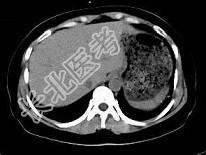

- 单项选择题根据所提供的图像,最可能的诊断是 ( )

A、正常肝血管

B、肝内胆管扩张

C、布-加综合征

D、肝血管瘤

E、以上都不是